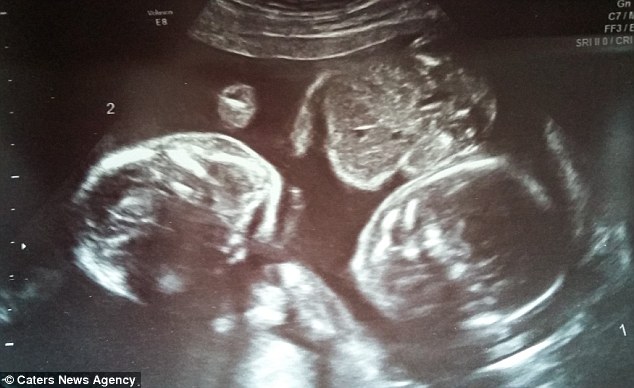

The picture on this page is an untouched photograph of a being that has been within its mother for 20 weeks. Please do me the favor of looking at it carefully. Have you any doubt that it is a human being? If you do not have any such doubt, have you any doubt that it …